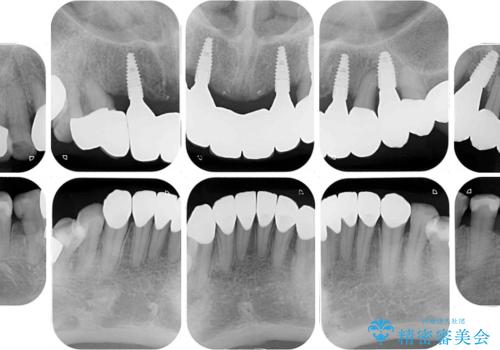

- 全顎的な歯肉からの出血と前歯の形態を気にして来院された患者様です。

診査の結果、上顎奥歯を中心に深い歯周ポケットが認められたため、歯周ポケット除去を目的とした歯周外科処置を行うこととしました。

また、前歯のブリッジへの咬合力の負担が大きく、土台となっている歯が揺れてしまっていたため、インプラント埋入により奥歯への負担を軽減することとしました。